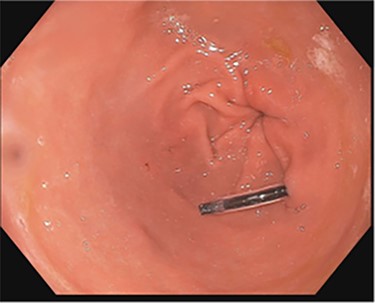

A 43-year-old incarcerated woman with borderline personality disorder and a long history of swallowing various foreign objects in periods of stress presented to the emergency department after swallowing a cup of bleach. Her surgical history was significant for multiple celiotomies for retrievals of purposefully ingested foreign bodies. During evaluation, she also admitted to swallowing an ink pen 3 weeks prior to swallowing the bleach for which she did not seek medical evaluation. She reported no food intolerance or changes in bowel function secondary to swallowing these objects. She presented with mild abdominal pain and cramping, and her vital signs and laboratory investigations were all within normal limits. Her abdominal exam was notable for mild tenderness to palpation diffusely. Computed tomography (CT) of the abdomen (Fig. 4) showed a linear foreign body in the distal gastric antrum penetrating the inferior wall and extending into the adjacent peritoneal fat. No free air or free fluid was appreciated. Initial esophagogastroduodenoscopy (EGD) was significant for mild erythema and edema to the esophageal and duodenal mucosa as a result of the caustic ingestion, and the pen was found to be deeply perforating the stomach antral wall with no associated ulcer or edema (Fig. 1). The depth at which the foreign body was lodged was uncertain, so there was concern for organ involvement outside of the gastric wall. Repeat EGD was done to assess for manifestations of esophageal, gastric or duodenal injuries from her caustic ingestion, and it revealed normal gastric mucosa (Fig. 2). A joint case was planned with the gastroenterology service for endoscopic foreign body retrieval, possible laparoscopic retrieval and gastric repair and possible open retrieval and gastric repair. The patient was taken to the operating room for the third EGD, which revealed spontaneous migration of the foreign body from the perforation site into the lumen of the gastric body (Fig. 3a). Additionally, there was spontaneous closure of the site of previous perforation (Fig. 3b and c). The ink pen was easily removed transorally using an endoscopic snare, and no further surgical intervention was required. After the procedure, the patient reported complete resolution of her abdominal pain and was able to tolerate a regular diet without problems.

EGD on initial presentation; gastric antrum with foreign body perforating through the gastric wall.